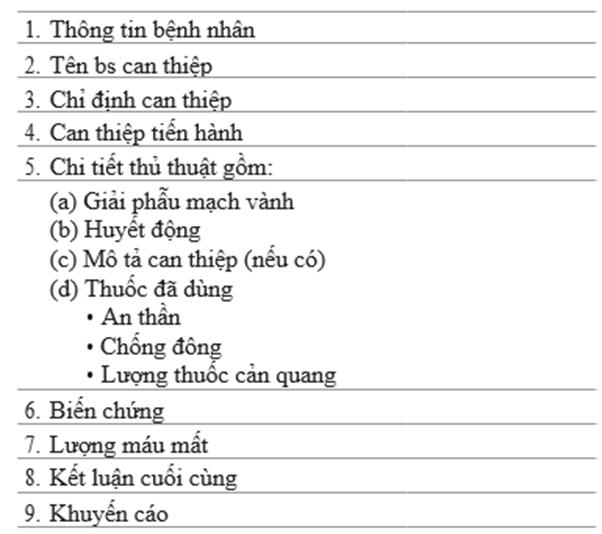

7. khi kết thúc thông tim, cần có báo cáo hoàn chỉnh để có thể có thông tin cho can thiệp và tham khảo sau này. Table 71.5 tóm tắt các thông tin cần có trong báo cáo

Table 71.5 thành phần trong báo cáo